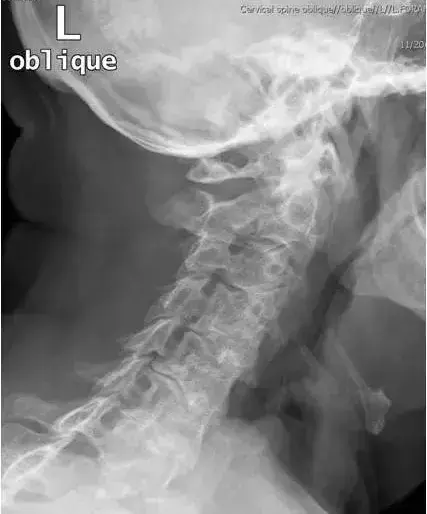

图3、正常颈椎双斜位

图14:颈椎左前斜位。右侧C3-C4和C5-C6孔的轻度狭窄和右侧C4-C5孔严重狭窄。

图15:颈椎左前斜位。左C4-C5和C5-C8孔的狭窄。